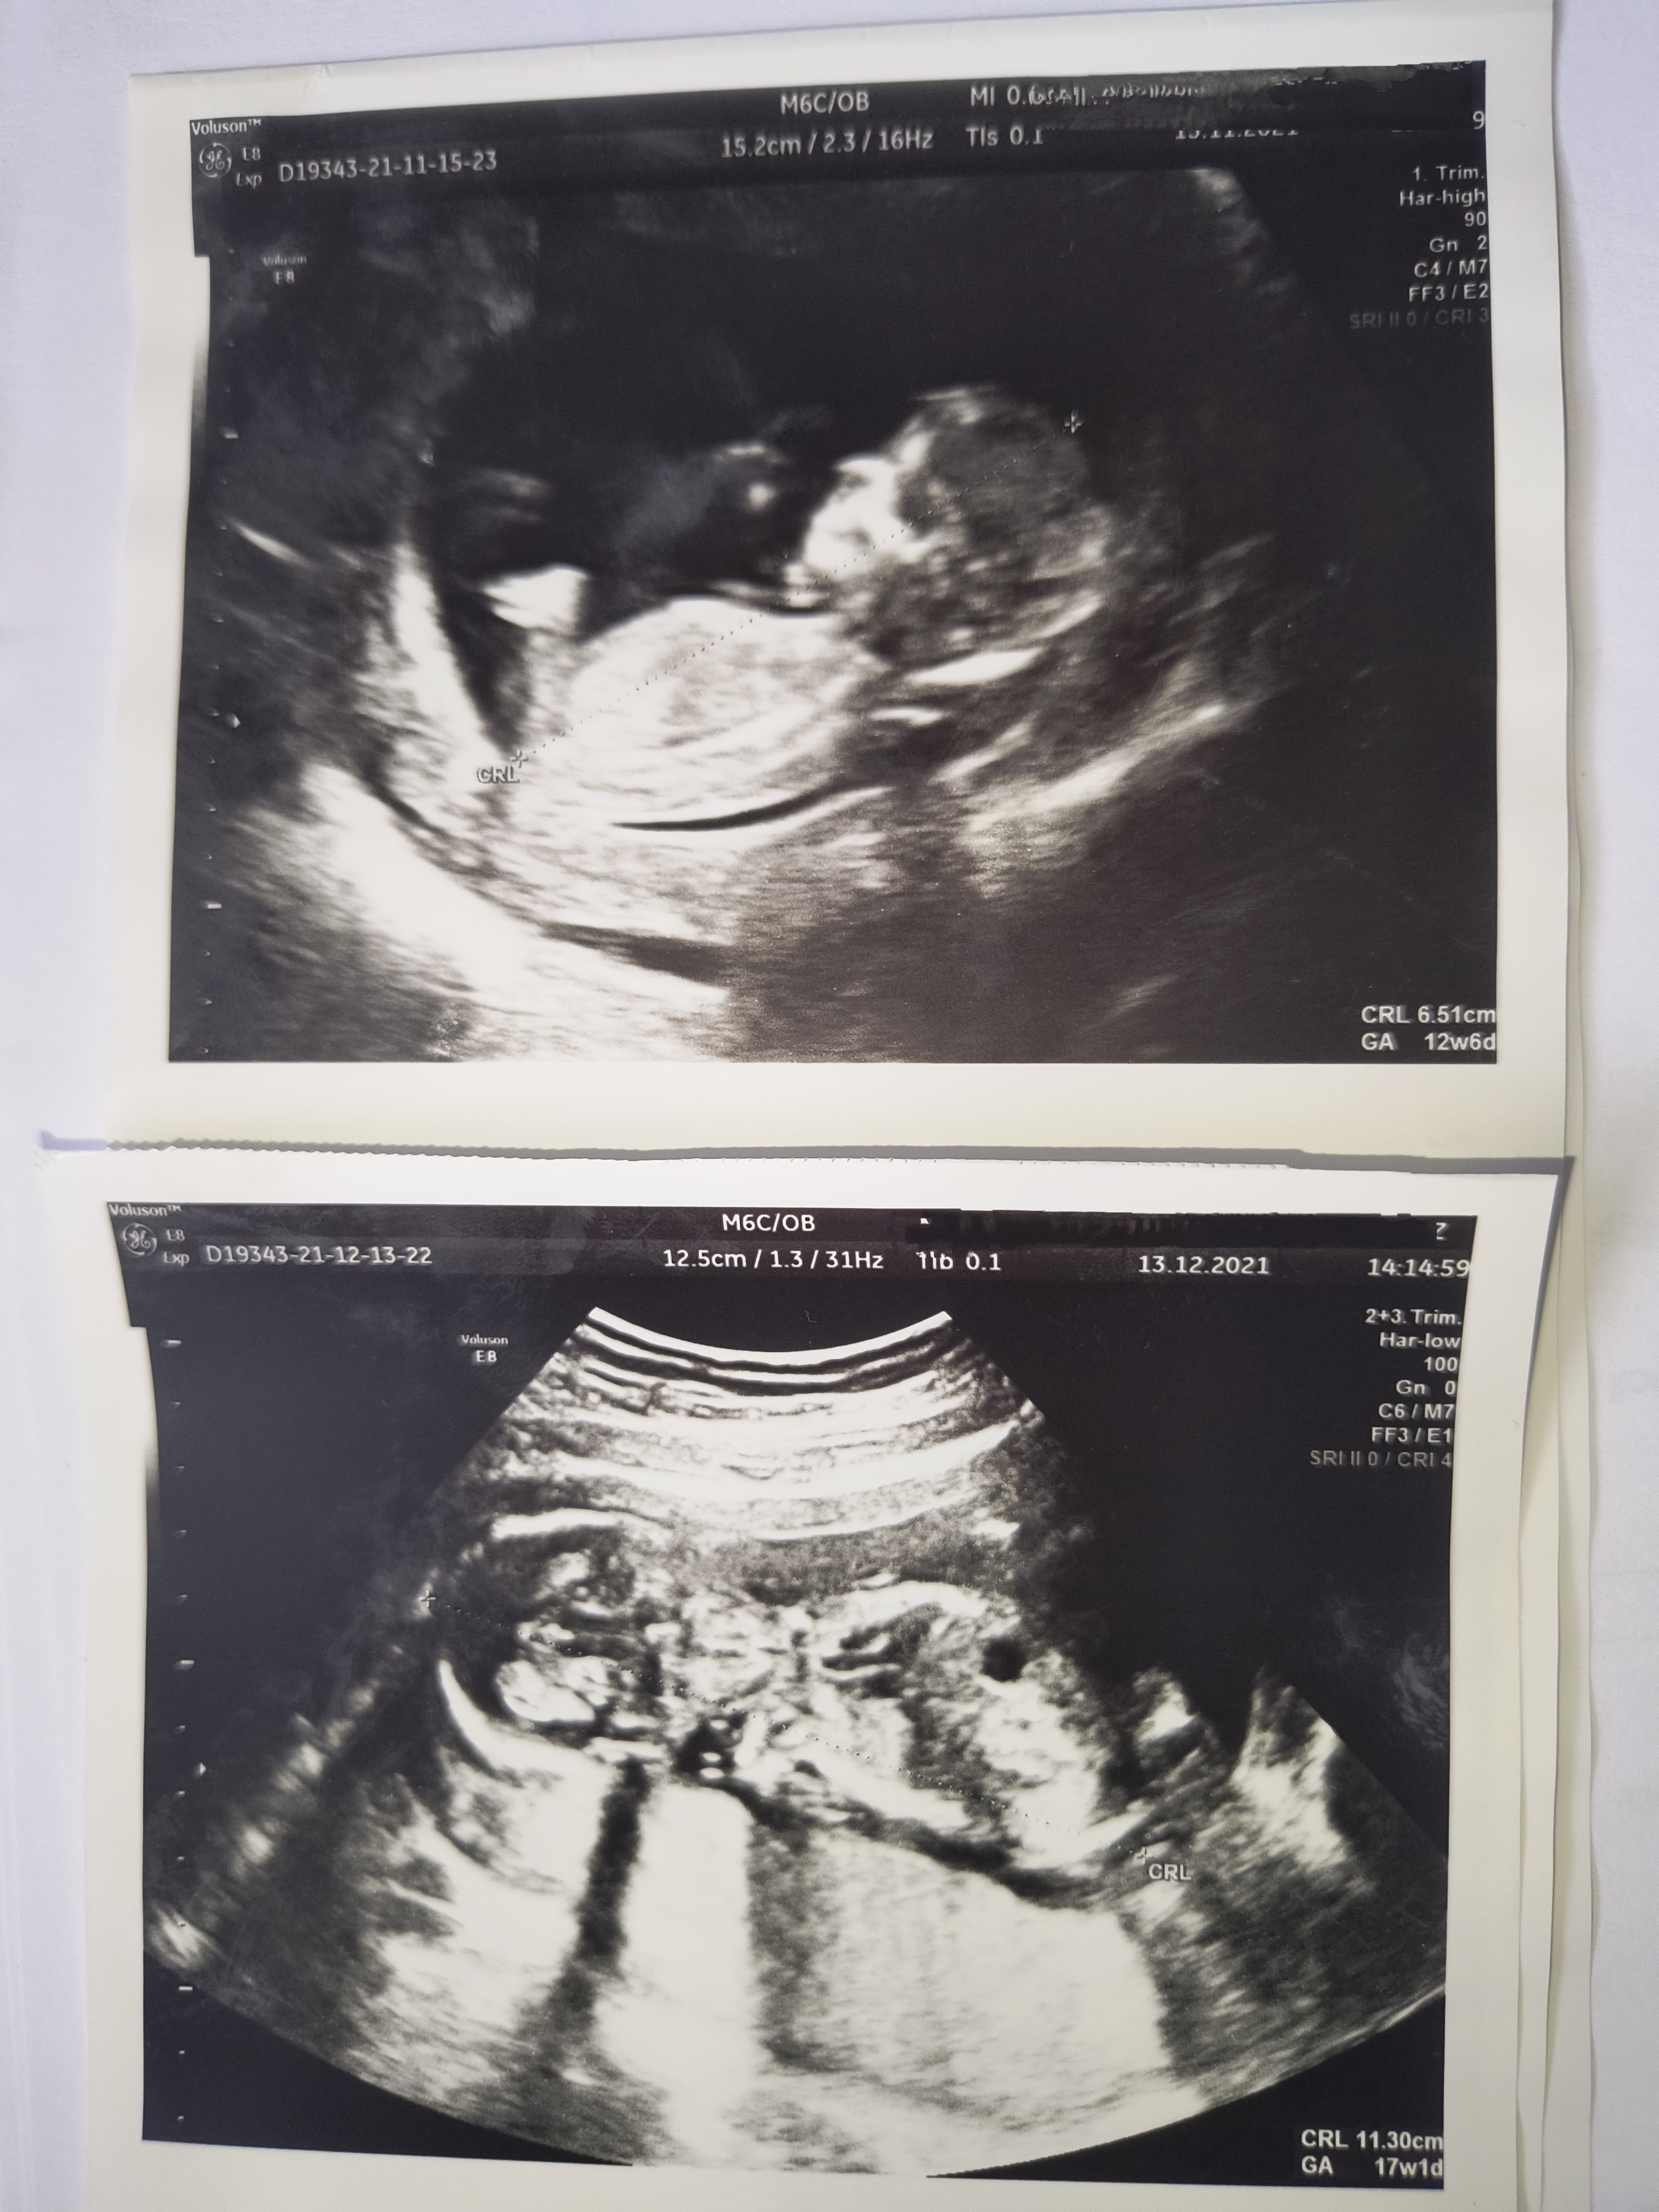

Wygląda jakby wyrostek szedł poziomo - czyli dziewczynka - ale jeszcze jest czas na płeć i słabo trochę widać. A masz jakieś przeczucia co do płci?Część dziewczyny, powiedzcie czy widzicie jaka płeć? Jestem w 18tc +4 dni![]()